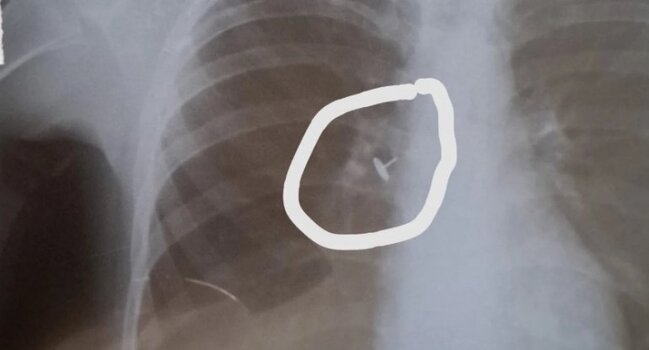

"Uşaqdan gecələr yatanda qəribə səs gəlirmiş, öskürək, xışıltı narahat edirmiş. Anası uşağı həkimə apararaq rentgen etdirib. Rentgen şəklində bronxda ilişib qalan yad cisim açıq-aşkar görünsə də, həkim uşağa soyuqlama əleyhinə müalicə yazıb. Bir aydan çox müddətdə uşağın düzəlmədiyini görən ana uşağı yenə rentgen etdirib və özü bu qeyri-adi görüntünün fərqinə varıb O, müqayisə üçün özü də ultrasəs müayinədən keçib.

Sonra mənə göndərdi ki, uşağın bronxunda olan nədir? Bu, udulmuş və nəfəs yoluna düşmüş bir knopkadır, aydın görünür. Amma necə olur ki, bunu həkim görmür, rentgen həkimi demir, uşağa soyuqlama müalicəsi yazılır? Mütləq şəkildə araşdırılmalı məsələdir. Bu məsuliyyətsizliyi edən valideyn deyil, həkimlərdir",- deyə o əlavə edib.